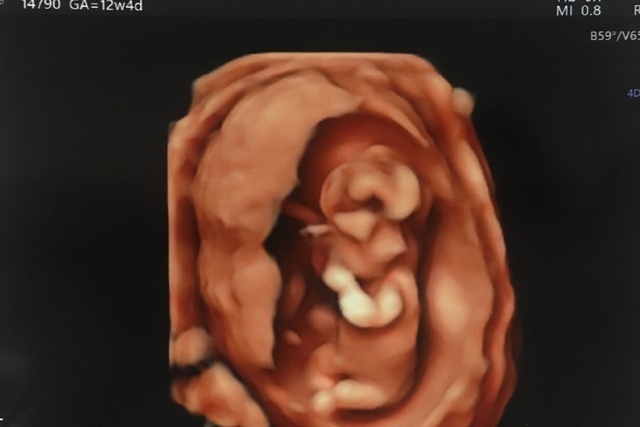

12週6日(12w6d・男の子)|chaa1015 さん(30歳)

エコー写真撮影時のエピソード:

4Dでの初めての撮影です。 普通のエコーと比べてとてもリアルで記念の1枚です!

検査中に手が動いている姿に夫と一緒に感動しました!4Dだからわかりやすいとは思いますが、どこがお顔かよくわかるように目をつけて両親などに報告しました。